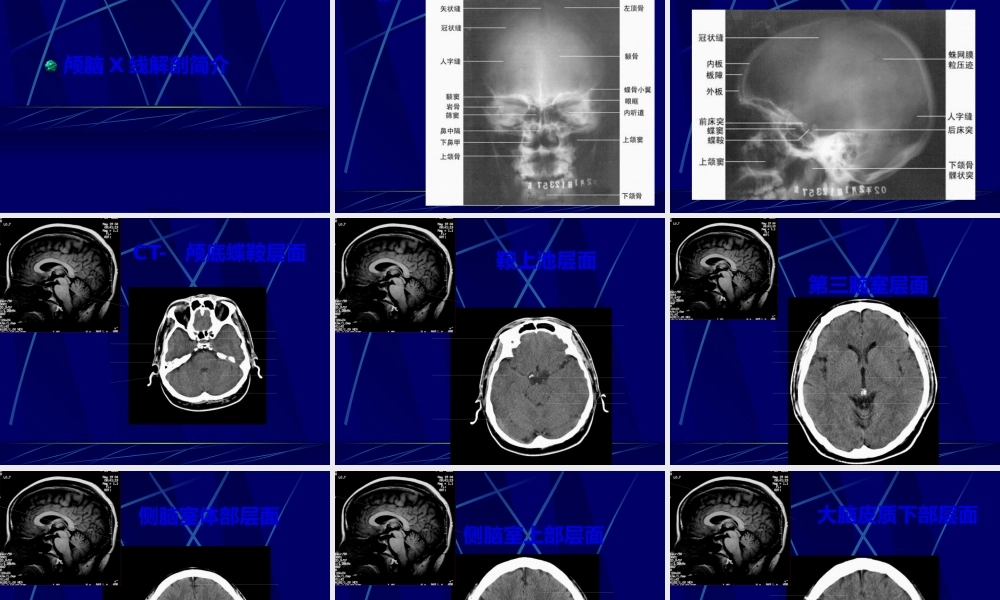

中枢神经系统正常及异常影像改变北京协和医院放射科第一页,共七十八页。中枢神经系统影像学技术颅骨平片脑血管造影脑CT脑磁共振第二页,共七十八页。头颅平片〔正侧位像〕第三页,共七十八页。头颅平片诊断价值有限•观察异物的存在和骨质结构的明显变化•显示骨折、肿瘤骨转移、网状内皮系统疾病、代谢性骨病、骨纤、畸形性骨炎等•观察颅骨骨折,有学者建议直接行CT•注意区分正常颅缝、血管沟和骨折线•有时可看见颅内钙化,如松果体钙化、肿瘤钙化等(中线钙化:松果体钙化、第三脑室脉络丛钙化、大脑镰钙化)•侧位可观察蝶鞍的形态,如扩大提示垂体瘤等,但不扩大也不能排除病变第四页,共七十八页。脑血管造影第五页,共七十八页。脑血管造影适应征•诊断脑动脉瘤、血管发育异常、血管闭塞•了解脑肿瘤的供血动脉•可同时行介入治疗•溶栓•Coil〔螺圈〕闭塞动脉瘤和血管畸形等•术前栓塞富血管性肿瘤如脑膜瘤•其他第六页,共七十八页。第七页,共七十八页。NeuroCT----CT在CNS的应用•CT平扫•疑心急性颅内出血的首选检查手段•假设CT已有堵塞征象,那么不应系统溶栓•CT血管造影〔CTangiography,CTA)•识认血管•其他最新应用•CT脑灌注成像〔CTperfusion)第八页,共七十八页。MRItips•主要基于3个可变的生物学参数:•质子密度〔protondensity〕•纵向驰豫恢复时间〔T1relaxationtime)•横向驰豫恢复时间〔T2relaxationtime)•通过采用不同的脉冲序列和不同的成像参数,获得反映上述生物学参数比照的MR图像,即质子密度加权像〔PDWI)、T1加权像〔T1WI)和T2加权像〔T2WI)•这些图像上的信号强度与特定的组织特征有关。•比方:血肿的化学和物理结构随时间而变化,直接影响其MR图像的信号强度•由此提供出血时间的信息,急性?亚急性?还是慢性?第九页,共七十八页。其他方法•气脑造影及脑池造影Airencephalographyandcisternography•有创性检查,现已根本不用。•USG•用于囟门未闭的婴幼儿,观察脑内结构;•TCD:检测颈部及颅内动脉血流动力学变化,了解头颈部血管病变的情况。第十页,共七十八页。PartII:imagingfeatures中枢神经系统正常及异常影像学表现第十一页,共七十八页。MRI图像T1加权像:--看正常解剖---脑脊液和房水是黑的灰质比白质暗〔就像真的〕T2加权像:--看病理改变---脑脊液和房水是白的灰质比白质亮第十二页,共七十八页。骨皮质骨髓质脑膜脑脊液脑白质脑灰质血管T1WI低信号高信号低信号低信号高信号等信...